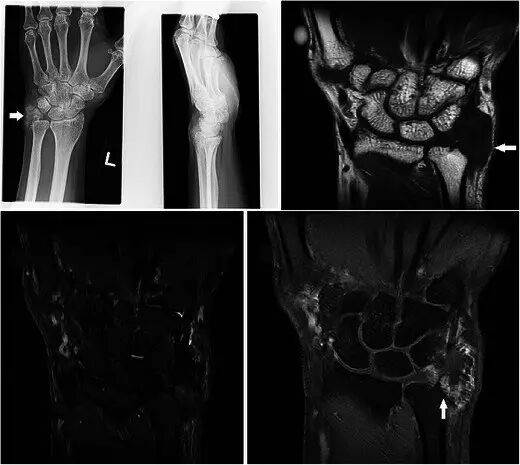

腱鞘巨细胞瘤Giant cell tumour of tendon sheath GCTTS是常见的肿瘤,通常在30-50岁时表现为无痛的肿块,具有轻微的女性偏好。 它们通常存在于与退行性关节相关的手或脚中,并且被认为是对邻近炎症的反应性损伤而不是真正的肿瘤[40]。 GCTTS在组织学上是良性的,但是在10-20%的病例中,在平片上可以看到相邻骨的压力变化[41](图13a)。MR显示与关节和腱紧密相关的损伤,主要是T1w序列上的低信号和T2w序列上的中等至稍高的信号(图13b-e)。 GRE序列上可见典型的异常图像,因为血铁素沉积,这是一个有用的特点[42]。 由于在胶原基质中存在许多增殖性毛细血管,观察到强的增强。 鉴别诊断包括局灶性结节性滑膜炎,其还含有铁氧化物,而更加异质的信号和增强可导致与软组织肉瘤的混淆。

图13.GCTTS在一名23岁的女性,有1年的右拇指肿胀和轻度疼痛的病史。 (a)平片显示在第一掌骨(箭头)的头部的明确的透亮区。 (b)T1w序列显示包围屈肌腱长肌的中间信号的分叶皮下病变(箭头)。 (c)病灶在T2w-FS序列上显示不均匀高信号。 在下面的骨头上有压力侵蚀。 (d)在GRE序列(箭头)上证明了易感性的Foci。 (e)有积极和相当均匀的增强

恶性骨病变Malignant bony lesions 骨转移到手(acrometastases)是罕见的。 恶性肿瘤的最常见的原发部位是肺,肾和乳腺,并且它们通常表示不良预后[49]。显示出膨胀性破坏性溶骨性破坏X线平片通常是在适当的情况下可以下(图18)诊断。如果对临床病史或异常放射照相外观有任何不确定性,MR可能是有用的(图18b-d)。治疗是姑息治疗,但可以提高生活质量。

图18.一个67岁男性的肺腺癌病史的骨转移,在右侧背部的内侧方面呈现2周的肿胀和疼痛病史。 (a)平片显示第五掌骨的透性破坏(箭头)。 (b)T1w序列显示具有浸润性软组织,主要是异质中间信号的第五掌骨的破坏。 (c)病灶在T2w-FS序列上是非均质的高信号。 (d)看到延伸到相邻软组织的非均匀增强

软骨肉瘤是成人中最常见的原发性骨恶性肿瘤,并且可以作为良性软骨瘤损伤(例如软骨瘤)的恶性变性发生。 平片显示典型的“环 - 弧”矩阵,其具有内皮层扇形和皮层变薄,但是在更高级别的亚型中,经常存在骨折破坏和不规则边缘[50](图19a)。 MR通常用于局部分期(图19b-d)。 对远端指骨的病变的鉴别诊断是血管球瘤,但是显示主要可扩展的骨病变的平片显示有效地排除了它。

图19.低级软骨肉瘤在一个47岁的女性,呈现一个缓慢扩大的企业肿胀左侧小指的远指骨几个月与指甲畸形。 (a)平片显示在小指的远指节中的可扩张的裂解性骨病变,具有标记的内皮层破裂和随着背侧皮层的破坏而变薄。 环 - 弧密度暗示着软骨形成基质(箭头)。 (b)T1w序列显示在中指的小指远端指节中的可扩展的骨病变,软组织成分破坏并穿透背皮质以涉及皮肤和指甲。 (c)在具有低信号区域(箭头)的T2w-FS序列上,病变是非常高的信号,典型的软骨形成基质。 (d)后对比度有异质增强